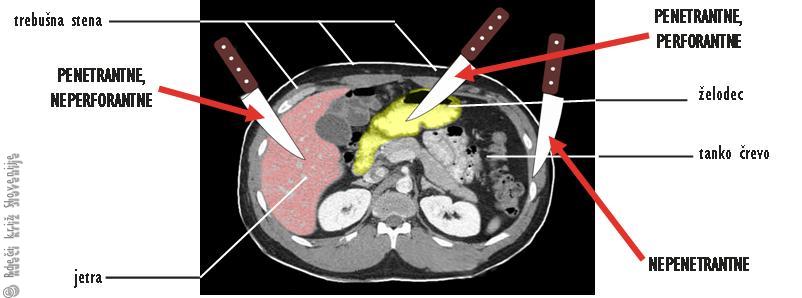

· Globino poškodbe (Slika 2):

· nepenetrantne rane – poškodba ne seže v trebušno votlino, potrebušnica ni bila prekinjena;

· penetrantne rane – poškodba seže v trebušno votlino in potrebušnica je poškodovana:

· neperforantne – votli prebavni organi niso poškodovani,

· perforantne – poškodovani so votli prebavni organi, katerih vsebina izteka v sicer sterilno (brez mikroorganizmov) trebušno votlino.

Slika 2

Glede na globino poškodbe ločimo nepenetrantne in penetrantne rane, ki so lahko neperforantne ali perforantne.